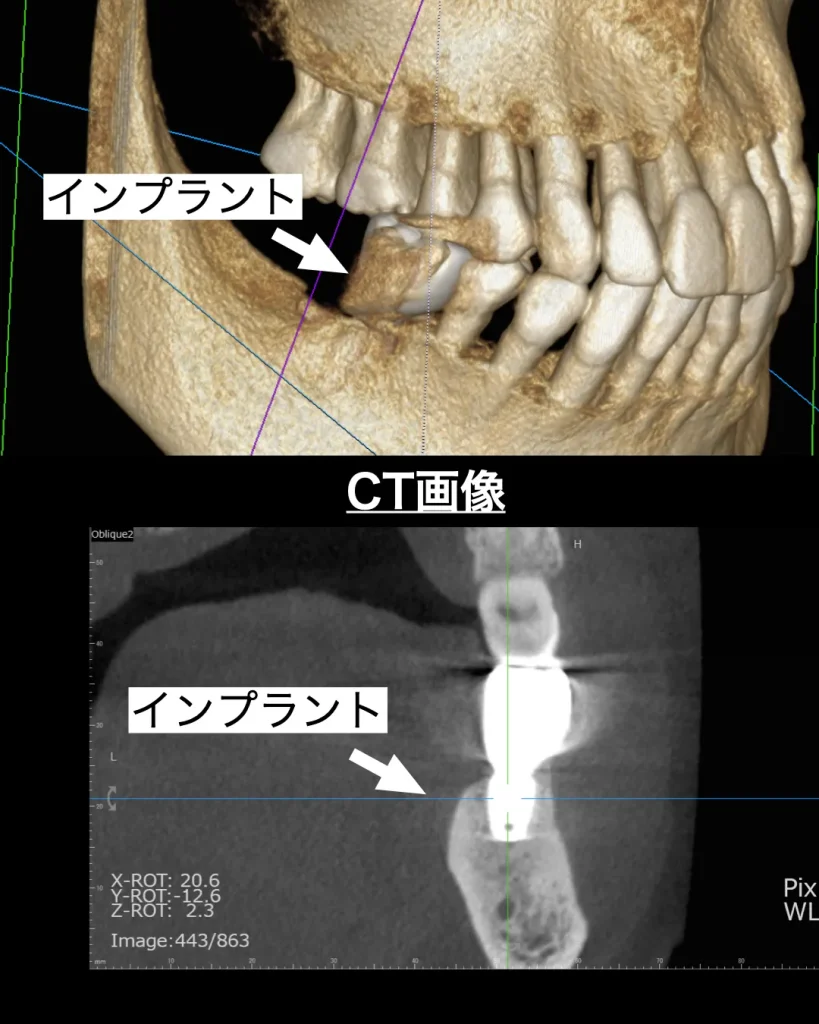

歯肉は2ヶ月ほどで治癒し、3ヶ月ほどで骨硬化像もでてきました。ISQと呼ばれるインプラントが骨と生着し硬くなっている値を測定する機械で測ると十分な値を得ることができました。仮歯の型採りを口腔内スキャナーで行い、セットし、頬を噛まないか・舌を噛まないか・しっかりとお食事ができるかをチェックし、問題ないことを確認しました。

セットまで3ヶ月ちょっとで終了することができ、患者様は大喜びされました。これは抜歯即時インプラントができたことによるものです。

患者様には1番奥の歯の治療もお勧めさせていただきました。なぜなら上の歯が伸びてきており、今後もさらに伸びてくる可能性があり、噛み合わせのバランスが崩れることがあるからです。患者様にはご納得いただき、近い将来ぜひ治療したいとおっしゃっていただけました。今回の治療が痛みなく、早く終了したことにもご満足いただけました。